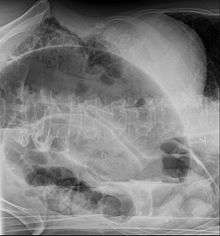

After taking a thorough history, the diagnosis of colonic volvulus is usually easily included in the differential diagnosis. Abdominal plain x-rays are commonly confirmatory for a volvulus, especially if a "bent inner tube" sign or a "coffee bean" sign are seen. These refer to the shape of the air filled closed loop of colon which forms the volvulus. Should the diagnosis be in doubt, a barium enema may be used to demonstrate a "bird's beak" at the point where the segment of proximal bowel and distal bowel rotate to form the volvulus. This area shows an acute and sharp tapering and looks like a bird's beak. If a perforation is suspected, barium should not be used due to its potentially lethal effects when distributed throughout the free infraperitoneal cavity. Gastrografin, which is safer, can be substituted for barium.

- Abdominal x-ray – tire-like shadow arising from right iliac fossa and passing to left

- Upper GI series